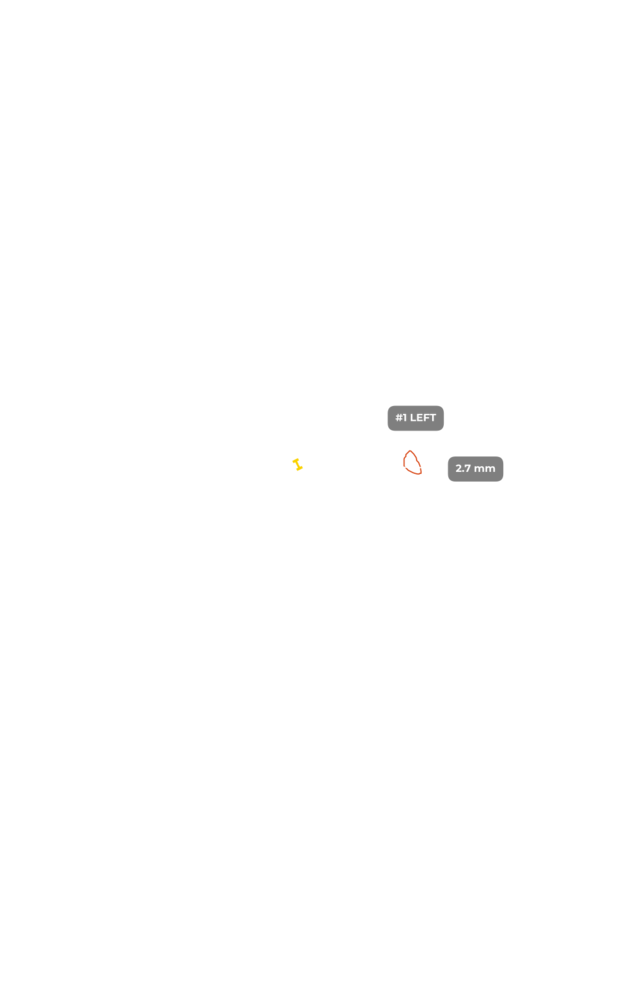

ИИ и алгоритмы интеллектуального анализа для рентгена коленного сустава. Оцените дегенеративные процессы менее чем за 1 минуту